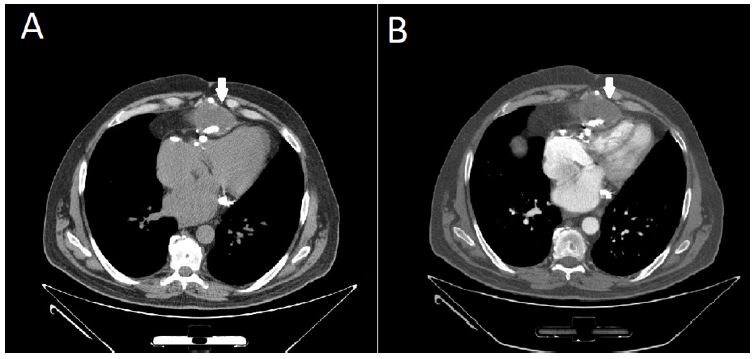

Among the results of the investigations carried out, the following are worth mentioning: Echinococcus IgG serology (by chemiluminescence immunoassay method) resulted negative; nucleic acid amplification for Entamoeba histolytica/dispar on feces resulted negative; QuantiFERON-TB Gold Plus (QFT®-Plus; Qiagen) resulted positive, suggesting a tubercular infection (at least a latent infection). A contrast-enhanced chest CT scan ruled out pulmonary parenchymal involvement but revealed extension of the mediastinal collection both above and below the diaphragm, with contact noted with both the pericardium and the hepatic capsule. Notably, the cyst capsule did not show ring enhancement after contrast, as was expected by a collection of infectious origin (Figure 1). Moreover, the chest CT showed numerous calcifications in the pericardial area (Figure 2). Following multidisciplinary discussion, on November 16, 2022, the patient underwent surgery for the removal of the cystic formation. Intraoperative samples revealed acid-fast bacilli, identified by nucleic acid amplification (Xpert® MTB/RIF; Cepheid) as rifampin-susceptible M. tuberculosis complex, subsequently confirmed by traditional mycobacterial culture to be pan-susceptible M. tuberculosis. Sputum and bronchial aspiration cultures were negative for acid-fast bacilli. Based on the findings from the intraoperative samples, antitubercular therapy was started using a standard intensive phase regimen (rifampin 10 mg/kg/day, isoniazid 5 mg/kg/day, pyrazinamide 25 mg/kg/day, ethambutol 20 mg/kg/day).

Figure 2: Sagittal chest CT scan. The cyst capsule is marked with a white arrow. Numerous calcifications are visible in the pericardial area.